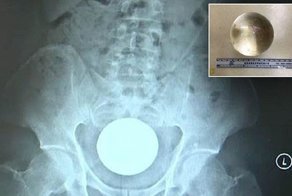

- Китайца доставили в больницу с 8-сантиметровым шаром в прямой кишке